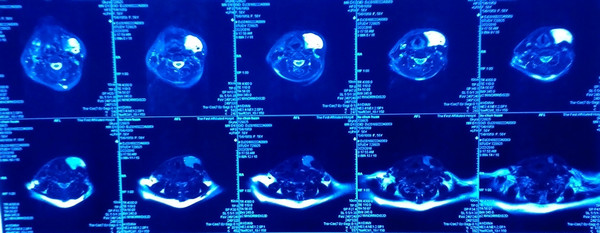

术前MRI示左颈部血管瘤

平顶山的刘女士受脖子包块的压迫已经近3年了,坐起来的时候包块缩小,但是一低头或者平卧包块就会明显变大,局部胀痛,脖子上的“大疙瘩”也严重影响外观。晚上平卧睡觉时,局部疼痛且呼吸不畅,必须枕着很高的枕头才能安眠,苦不堪言。于是前往省内某三甲医院就诊,查磁共振显示左颈部血管瘤,瘤体与颈内静脉沟通,因为没有颈部血管手术经验,于是建议转郑州大学五附院血管外科治疗。患者转入后,医院副院长、血管外科专家王兵教授仔细查阅了片子,给刘女士制定了详细的诊疗方案,因患者同时还合并双下肢静脉曲张,于是决定颈部血管瘤与双腿的静脉曲张同期手术处理。